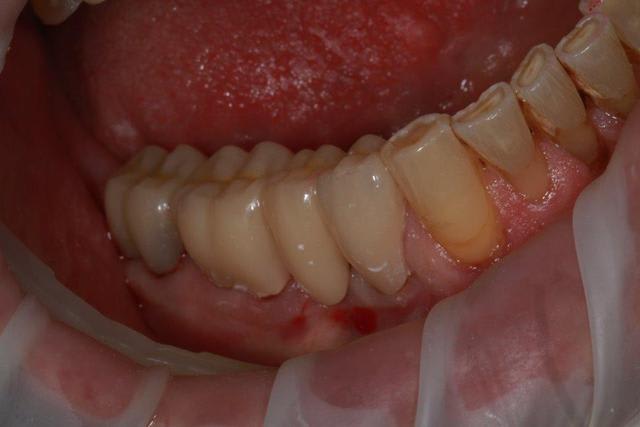

Nouveau patient, pose d'un implant il y a 2 mois....échec sans raisons particulières, douleurs et dépose.

Ce matin repose d'un nouvel implant et comme je ne veux pas prendre de risque, et que les dents adjacentes doivent être couronnées, je pose un bridge en emax press, mais scellé au ciment provisoire...

Si l'implant va bien le bridge sera déposé, coupé, et 44/46 seront collées définitivement après traitement acide et silane.

Si par hasard l'implant pose problème, dépose et bridge collé.

alors là pas du tout, le patient vient me voir pour des implants, donc je fais une étude du cas absence des molaires supérieures, couronnes mandibulaires très ancienne 45 racine cassée, 44 dévitalisée mais passablement déchaussée, donc avulsion de 45 et pose d'un implant avant de refaire les couronnes 46/47 et l'ensemble.

Échec implantaire, et oui ça arrive, même dans un cas paraissant simple.

Dépose gratuite bien sur et repose gratuite aussi, le bridge n'est pas facturé non plus, il le sera sous forme de 2 couronnes que cette fois ci l'implant fonctionne ce que j’espère, ou laissé en bridge si l'implant devait être retiré.

Le fait de scellé au ciment temporaire ne pose en principe pas de problème pour 3 à 6 mois.

dans le cas présenté, le but est de redonner confiance au patient, et pas du tout le fric.